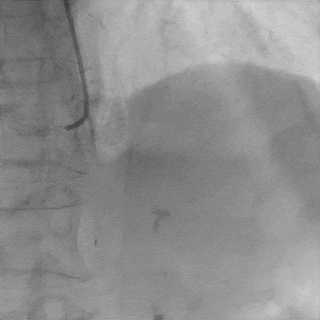

处理RCA病变:

Runthrough导丝至RCA远端,预扩球囊扩张RCA近中段病变处

植入支架Tivoli 2.75*18mm一枚

高压球囊后扩张后,无残余狭窄,血流TIMI3级